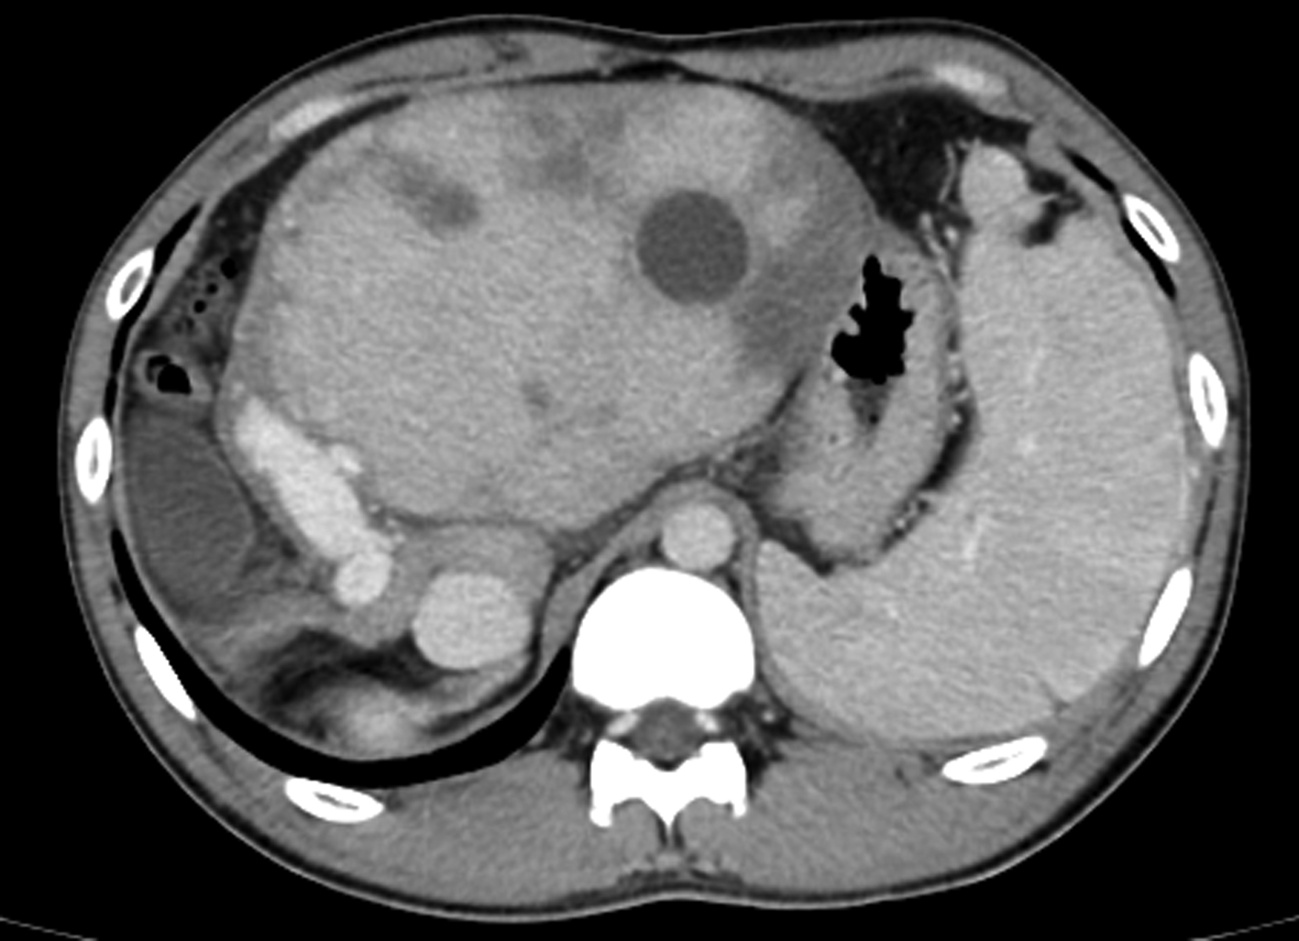

基于超声造影LI-RADS特征的肝细胞癌微血管侵犯列线图模型的构建及验证

2022, 38(11): 2520-2525. DOI: 10.3969/j.issn.1001-5256.2022.11.016

摘要(882) HTML (345) PDF (2938KB)(63)

摘要:

目的  基于肝细胞癌(HCC)患者的超声造影(CEUS)肝脏成像报告和数据系统(LI-RADS)特征建立预测微血管侵犯(MVI)的列线图模型并进行验证。  方法  选取2017年1月—2020年7月在江苏大学附属武进医院确诊的HCC患者共262例,按照1∶ 1比例随机分为建模组和验证组各131例,以术后镜下病理结果确诊MVI,其中建模组MVI 70例和验证组MVI 56例。采用超声造影评估两组的LI-RADS特征。两组间计量资料比较采用独立样本t检验;两组间计数资料比较采用χ2检验。采用单因素和多因素Logistic回归分析筛选建模组MVI的危险因素;绘制受试者工作特征曲线(ROC曲线),计算模型预测MVI的曲线下面积(AUC),评估预测准确度;应用决策曲线分析模型的一致性,比较模型预测MVI的校正曲线与标准曲线的离散度。  结果  建模组与验证组患者的临床资料和CEUS检查结果比较,差异均无统计学意义(P值均>0.05)。单因素分析显示,与MVI阴性患者相比,MVI阳性患者血清AFP水平显升高,肿瘤直径增大,LI-RADS显示LR-5“后出”和LR-M“先出”增多,LI-RADS分级较高,差异均有统计学意义(P值均<0.05)。多因素分析显示,AFP 20~400 ng/mL(OR=2.65,P<0.001)、AFP≥400 ng/mL(OR=3.98,P<0.001)、肿瘤直径≥30 mm(OR=2.12,P<0.001)和CEUS显示LR-M(OR=3.24,P<0.001) 是MVI的独立危险因素。ROC曲线显示,列线图预测建模组和验证组MVI的AUC分别为0.867和0.821。列线图模型的一致性指数C-Index为0.765(95%CI:0.701~0.834)。在建模组和验证组,列线图模型的预测校准曲线与标准曲线均接近。  结论  利用CEUS得出LI-RADS,并结合AFP和肿瘤直径建立的列线图模型有较好的应用价值,有助于指导临床术前筛选MVI高危患者,制订恰当的手术方案。